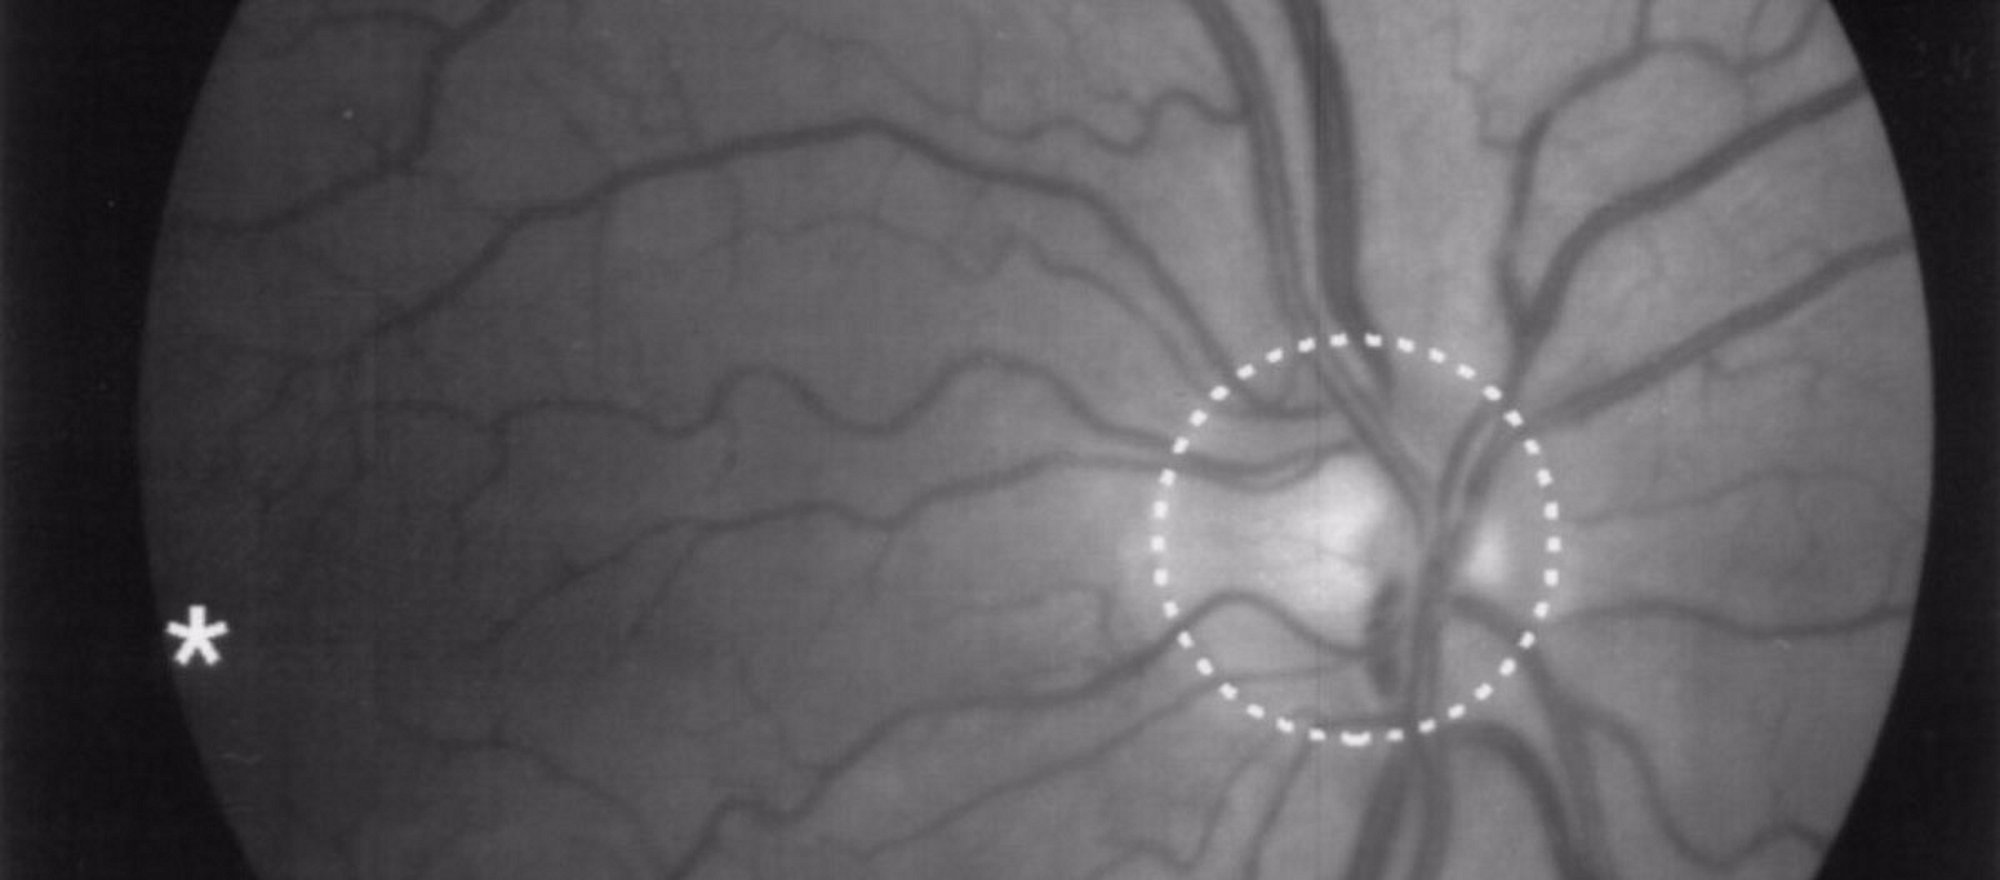

Görme yeteneğini kaybetmiş kişilere şimdiye kadar kök hücre tedavisi ve retinaya chip yerleştirme gibiretina-1 kısmen başarılı olan metotlar uygulanıyordu. Yeni keşfedilen basit ama etkili bir kimyasal madde görme yeteneğini kaybetmiş kişilere büyük umut vaat ediyor.

Retina körlüğüne çare olacağı tahmin edilen bu kimyasal madde, şimdilik farelerde denendi ve olumlu sonuçlar verdi.

Retina körlüğü bulunan farelerin gözüne damlatılan Acrylamide-Azobenzol-Quaternar-Ammonium (AAQ) adındaki bu kimyasal madde retina hücrelerini birkaç gün içerisinde ışığa duyarlı hale getiriyor.

Göze birkaç damla damlatılan AAQ, retinada bulunan iyon kanallarına yerleşerek onların açılmasına ve elektrik yüklerinin değişmesine sebep oluyor. Değişen elektrik yükü, sinir hücreleri üzerinde elektriksel impulslar oluşturarak retinaya gelen görüntünün beyne ulaşmasına ve orda görüntüye dönüşmesine olanak sağlıyor.

Bu tedavinin yaşlılığa bağlı makula(sarı nokta) dejenerasyonu* ile ileri derece retina hasarının tedavisinde iyi sonuçlar vereceği tahmin ediliyor.

Makula dejenerasyonu, sarı noktanın hasar görmesi veya ilerleyen yaşa bağlı olarak fonksiyon kaybıdır. Yüksek tansiyon, sigara ve genetik nedenler, makula dejenerasyonuna sebep olan diğer önemli risk faktörleridir.